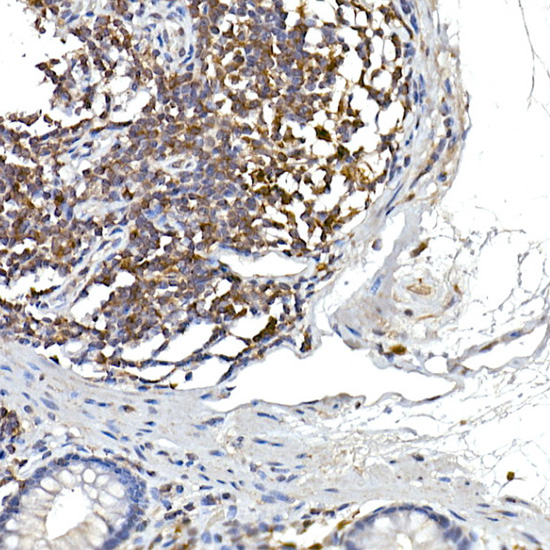

Immunohistochemistry of paraffin-embedded human colon using NFATC2 Rabbit pAb.

Immunohistochemistry of paraffin-embedded human tonsil using NFATC2 Rabbit pAb.

Immunohistochemistry of paraffin-embedded mouse spleen using NFATC2 Rabbit pAb.